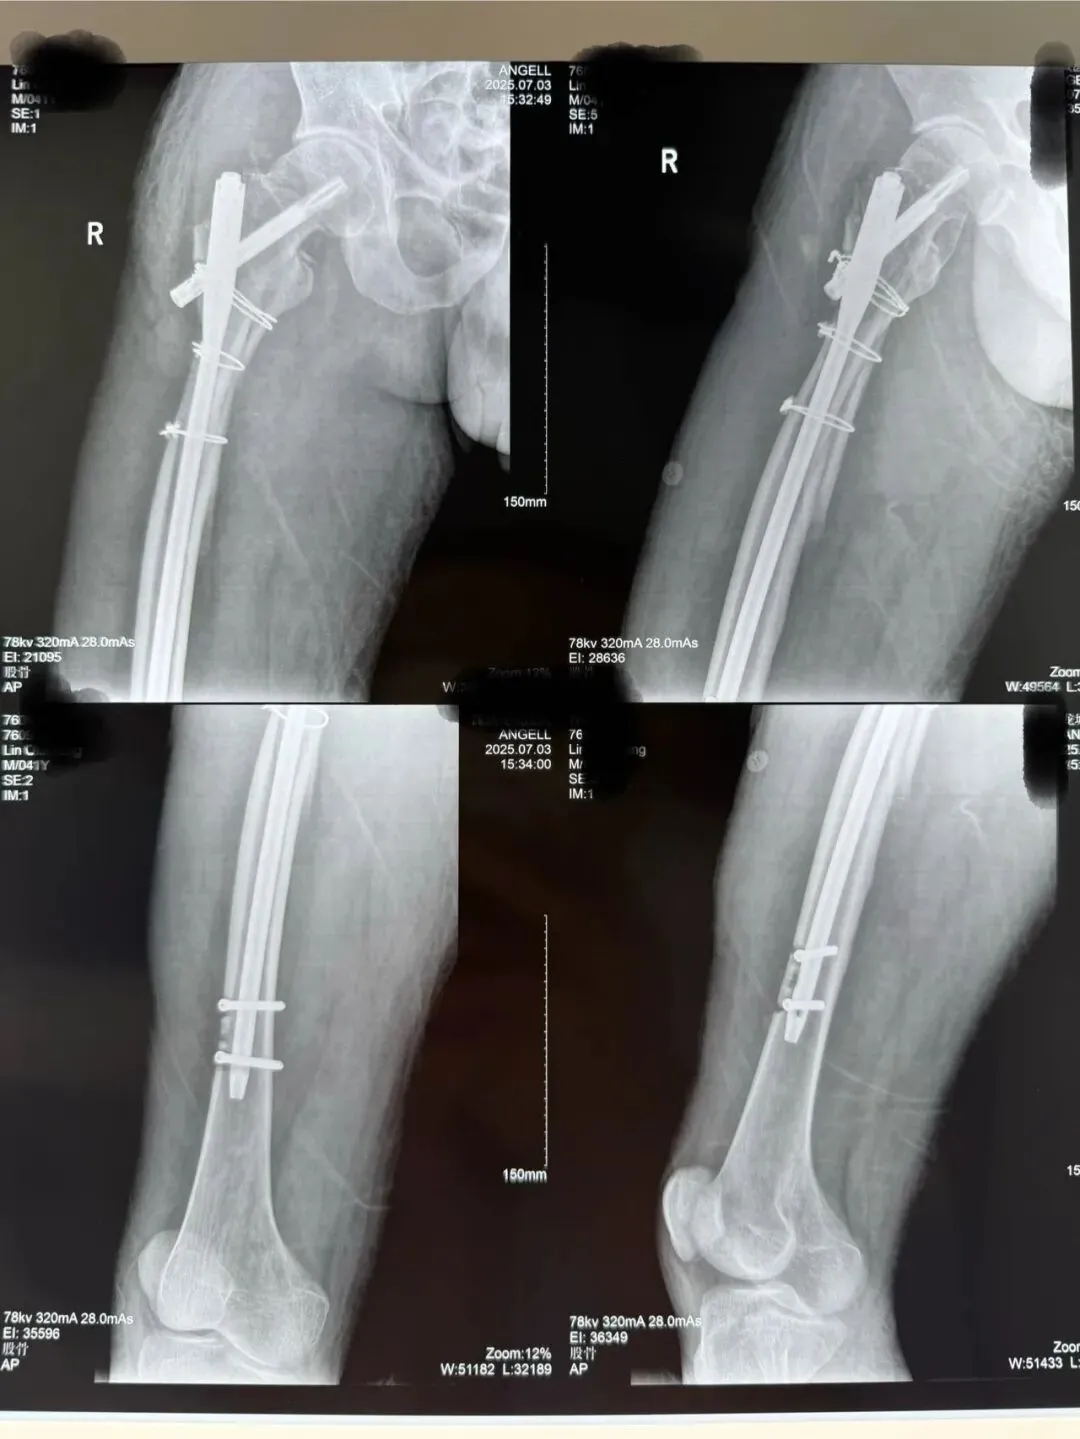

术后侧位看骨折块间仍有较大距离,但是我们不担心,骨折力线、颈干角没有太大问题。

术后两月半再看侧位,令人惊讶的事出现了,因为有软组织铰链夹板的保护,骨折块竟然向髓内钉周围汇聚到一起,骨折线完全消失。患者也完全能负重行走了。所以,遇到此类骨折,不管有多大难度,一定要最大程度的保护骨折周围软组织,让骨折块有活力,那样才能保证骨折顺利愈合。